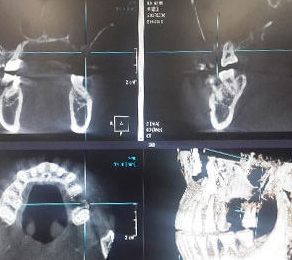

02. 3D-CT를 통해 사랑니의 크기와치아 방향, 깊이, 신경의 위치 확인

01. 안전한 시술을 위해 구강

검진과 함께 전신질환 체크

02. 3D-CT를 통해 사랑니의 크기와

치아 방향, 깊이, 신경의 위치 확인